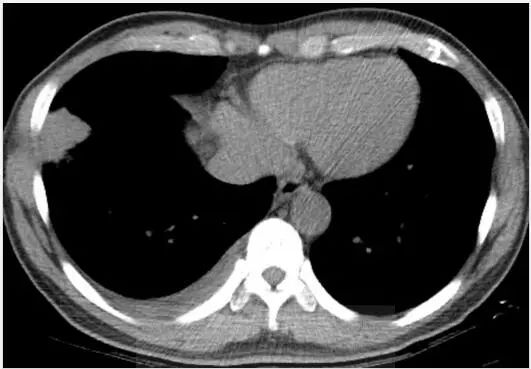

图2 示右肺下叶区域毗邻胸膜的分叶状肿块,以及重力依赖区域少量胸腔积液。